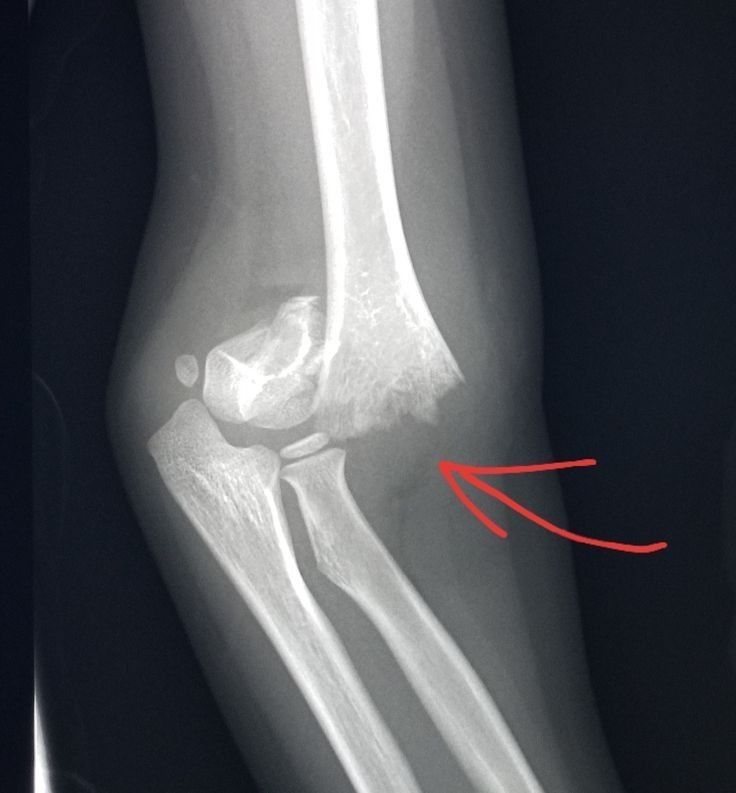

X-ray or CT/MRI

1. High-Impact Trauma

- Accidents causing severe joint injuries

- Sports or heavy-impact collisions

- Falls leading to joint instability

What imaging tests are needed before the surgery?

X-rays, CT scans, or MRI are used to understand the damage and plan the surgery with precision.